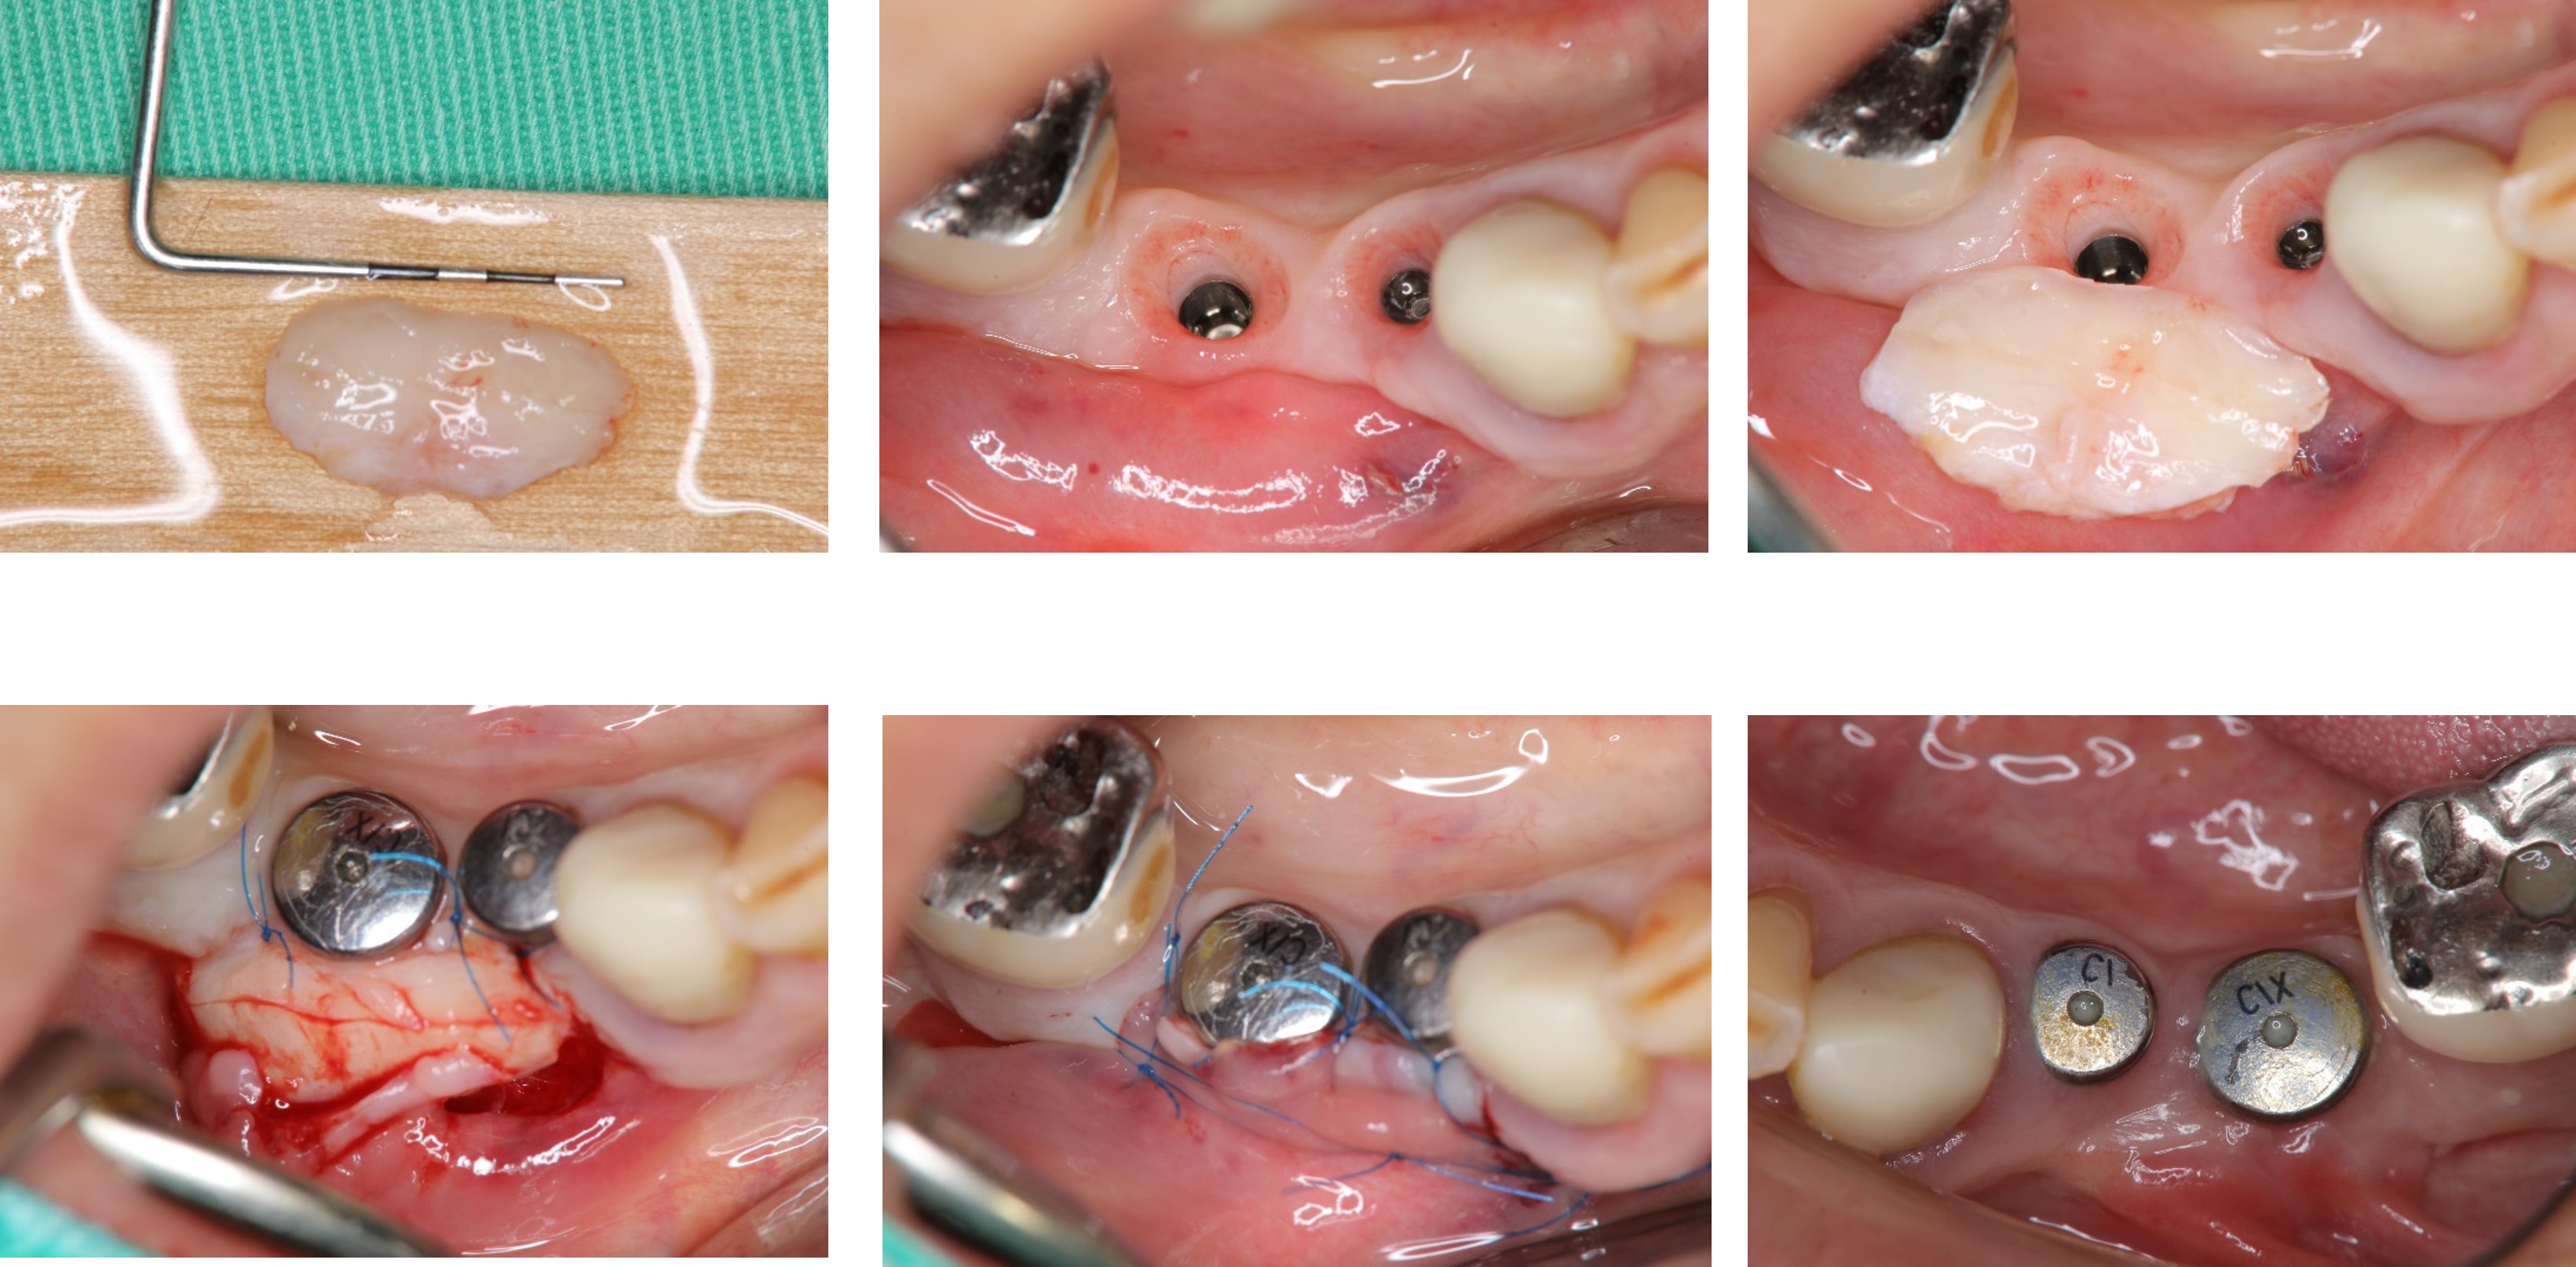

3)補皮手術

植牙穩定後修補角化牙齦